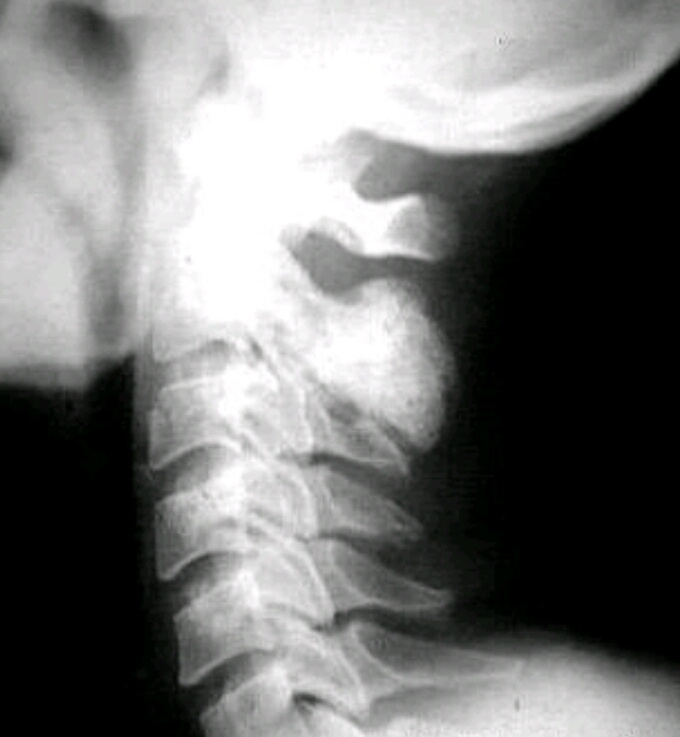

Findings? Diagnosis?

Sunburst periosteal reaction, dense sclerotic lesion at the proximal aspect of the humerus in the metaphyseal region, Codman triangle

Osteosarcoma